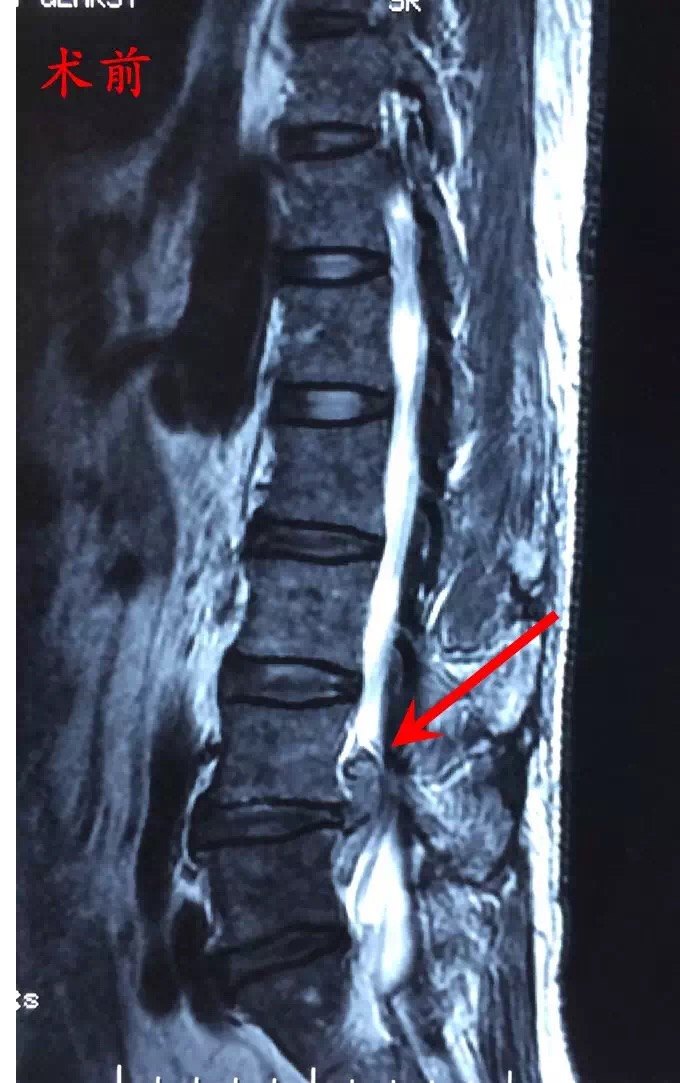

巨大型腰椎间盘突出症的微创手术治疗

1280x960 - 173KB - JPEG

680x1083 - 125KB - JPEG